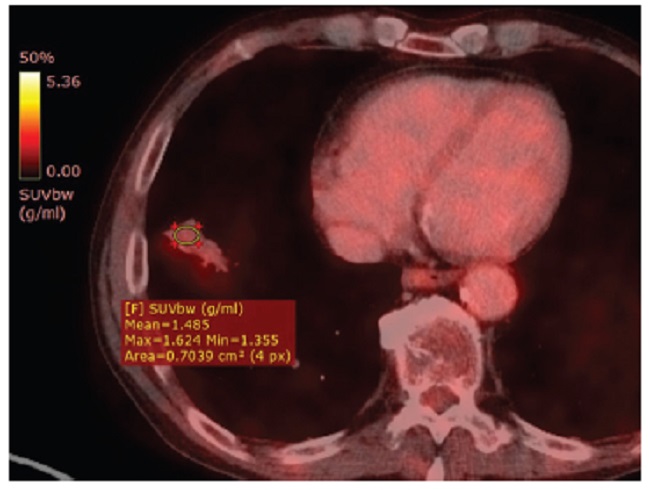

Presentamos el caso de un hombre de 67 años con diagnóstico reciente de carcinoma epidermoide queratinizante orofaríngeo, que en TC y PET-TC de estadificación presentó imagen pulmonar, consolidativa, en contacto con la cisura mayor y el domo diafragmático, con fino broncograma aéreo y reticulación perilesional (Fig. 1). Esta lesión demostró ser hipermetabólica con un SUV de 5,5 (Fig. 2). Dados los hallazgos, se realizó biopsia percutánea guiada por TC para confirmar secundarismo. Sin embargo, se identificó infiltración por población linfocitaria B de pequeño tamaño con perfil inmunohistoquímico positivo para CD20, bcl2 y Kappa, resultando negativo con CD3, CD5, Ciclina D1, CD10 y Lambda (Fig. 3). La citometría de flujo arrojó linfocitos B: 45,32%, población patológica: 96,06%, CD19+, CD20+, CD10-, CD5-, kappa+, CD23-, y CD43+ débil. Se arribó entonces al diagnóstico de infiltración por linfoma B de la zona marginal extraganglionar (MALT). Realizó tratamiento de inducción con esquema docetaxel, 5-fluouracilo y cisplatino. Luego consolidación con radioterapia y carboplatino concurrente. En la nueva PET-TC, seis meses más tarde, se pudo apreciar disminución de la captación de 18-fluorodesoxiglucosa (18F-FDG) y del tamaño de la lesión pulmonar (Fig. 4).